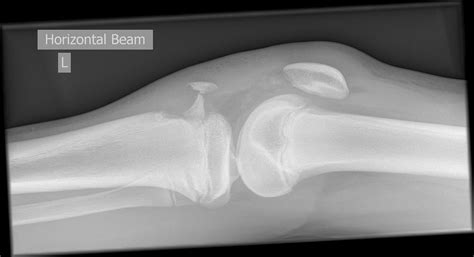

To confirm the diagnosis, physicians utilize a combination of physical examination and diagnostic imaging. Standard X-rays are typically sufficient to view the displacement, but in complex cases, an MRI or CT scan may be ordered to evaluate potential ligament damage or the involvement of the articular cartilage.